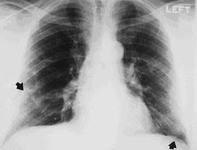

RT que demuestra engrosamiento pleural (se indica con las flechas)

De la colección personal de Kenneth D. Rosenman, Michigan State University